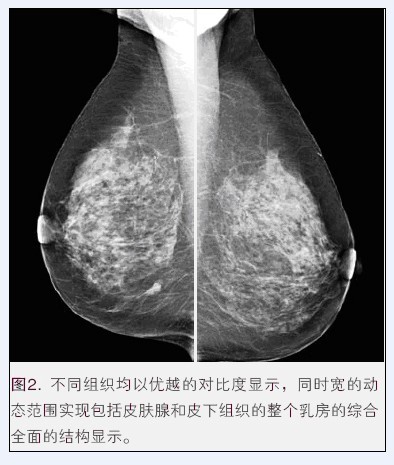

乳腺X射線機作為如今各大醫(yī)院及機構(gòu)主要的放射科設(shè)備之一,為女性健康提供了先進的檢測平臺,是如今醫(yī)學(xué)領(lǐng)域檢測患者乳腺癌變等狀況的必備醫(yī)療器械。然而,隨著醫(yī)學(xué)事業(yè)的快速發(fā)展,醫(yī)療器械行業(yè)發(fā)生了翻天覆地的變化,生產(chǎn)乳腺X射線機的醫(yī)療器械公司也越來越多,那么到底乳腺X射線機哪個牌子好呢?

這就不得不提到國內(nèi)具有較高知名度的普朗醫(yī)療。普朗BTX-9800系列乳腺機是如今女性乳腺癌早期診斷的金標(biāo)準(zhǔn),不僅可以發(fā)現(xiàn)0.1毫米的鈣化點,還能夠有效提示癌前病變,是乳腺炎癥、乳腺增生、乳腺纖維瘤等疾病監(jiān)測的必備設(shè)備。更多資料,點擊產(chǎn)品圖下方的紅色產(chǎn)品名稱進入指定頁面